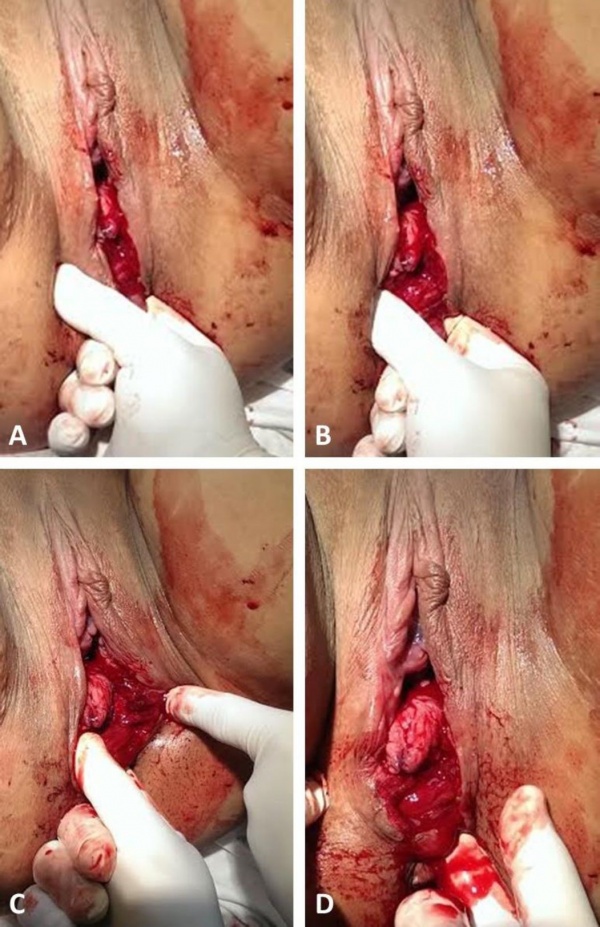

- יש לתקן את הסוגרים בהתאם לדרגת הקרע. רצוי לבודד ולזהות כל שכבה בנפרד (ראו נספח).

נספח - המלצות לתפירת הקרע[1]

- קרעים דרגה 4 המערבים את רירית פי הטבעת, רצוי לתפור את הרירית בתפרי (Vicryl (polyglactin 3-0 בודדים. אין חשיבות אם הקשר פונה לתעלה האנאלית או לצד הנגדי. מומלץ להימנע מתפרים כפולים (8 figure of) כיוון שיכולים לגרום לאיסכמיה של הרירית

- קרעים של סוגר פי הטבעת הפנימי (קרע דרגה 3c) רצוי לתקן את הסוגר הפנימי בנפרד ב־2-3 תפרי0–3 PDS או בתפרי 0–2 (Vicryl (polyglactin בשיטת U (דומה לשיטת end-to-end של הסוגר החיצון)

- קרעים של הסוגר החיצוני ניתן לתקן בשתי שיטות: End to end ו- Overlap

- קרע דרגה 3a (עד 50% מעובי הסוגר החיצון) רצוי לתקן בשיטת end-to-end בתפרי 0–3 WPDS בתפרי 0–2 (Vicryl (polyglactin

- קרע דרגה 3b (מעל 50% מעובי הסוגר החיצון) רצוי לתקן באם הקרע חלקי בשיטת end-to end, ואילו אם הקרע שלם שתי הגישות קבילות באותה המידה